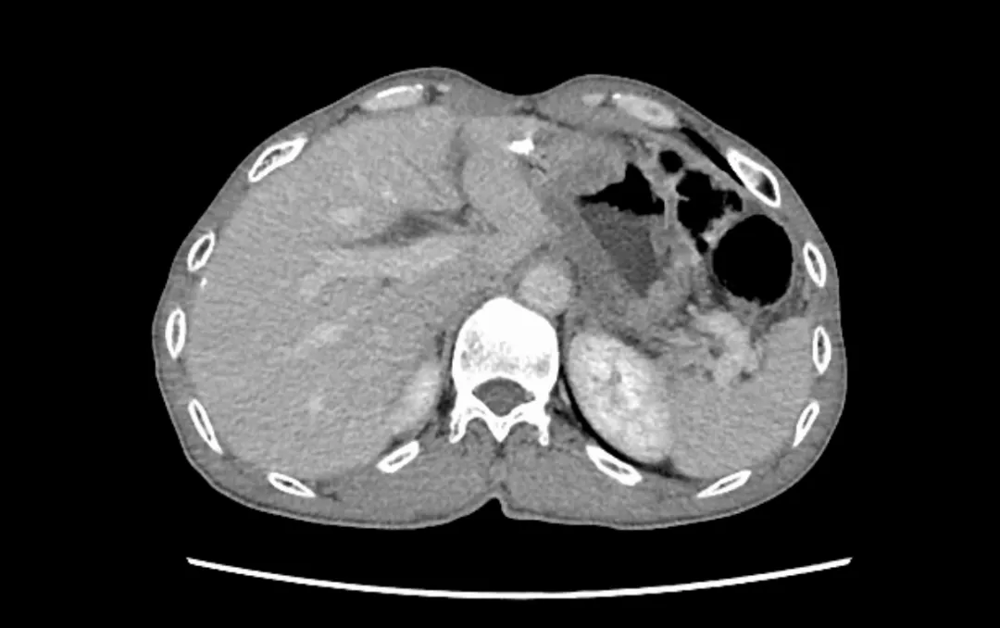

胃肠外科面对复杂、高风险的二次肿瘤手术展现出强大实力。一例66岁残胃癌复发患者,11年前曾行胃癌部分切除术,腹腔粘连严重,且合并肺气肿、营养不良等多重问题。胃肠外科牵头组织心内科、麻醉科、呼吸内科、影像科、临床营养科、中医科等进行多学科(MDT)会诊,制定了周详的个体化手术与围手术期管理方案。团队成功为患者实施了高难度的“残胃切除+食管空肠吻合+淋巴结清扫+粘连松解”手术。术后,针对患者出现的血压偏低等情况,心内科与中医科协同干预;临床营养科全程提供阶梯式营养支持。在多学科无缝协作下,患者平稳度过危险期,未发生严重并发症,顺利康复出院。该案例是我院利用多学科(MDT)综合诊疗模式优势处理复杂腹部肿瘤的成功典型案例。